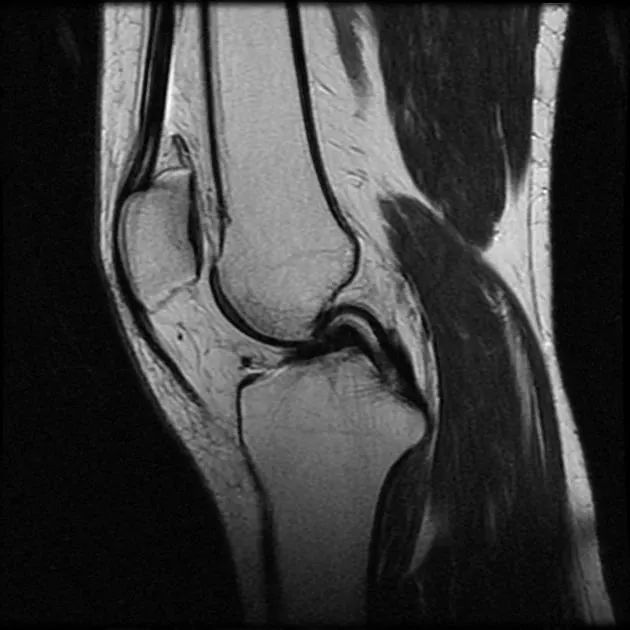

但是,有时我们却能看到“两条”后交叉韧带?

图2 膝关节正矢状位 MRI FS-T2WI 图像,红色箭头所指处可见两条低信号带,并列走行